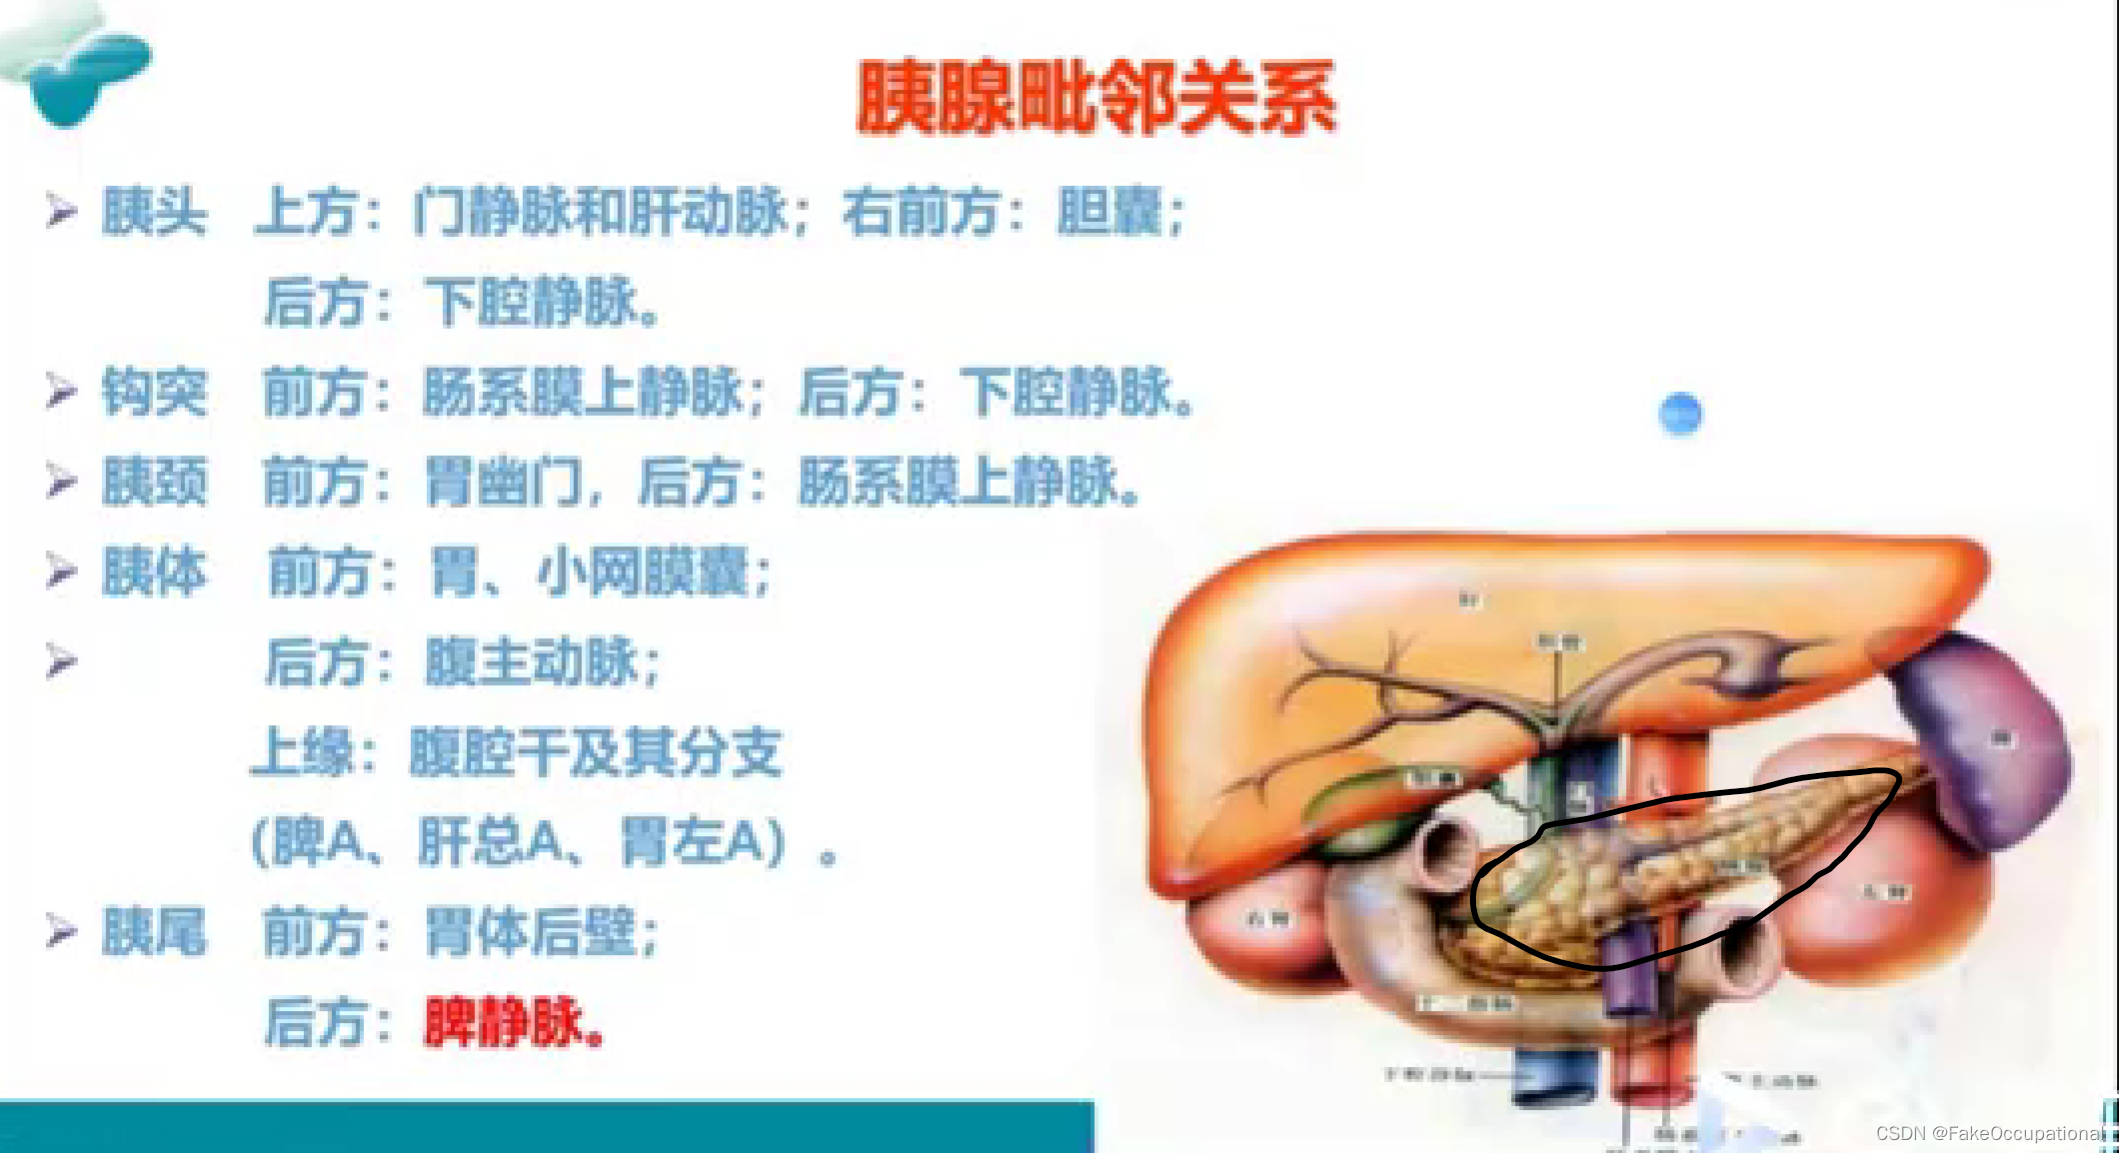

胰腺解剖及正常声像图

- 胰腺解剖与生理

腹膜后脏器 、无包膜、次于肝脏的大消化腺重约75克分内分泌部与外分泌部: 内分泌部分泌胰岛素,调节人体血糖浓度,外分泌部分泌胰液,有分解脂肪、蛋白质糖类的作用

位置: 胰腺的体表投影在脐上5cm-10cm处,位于第一第二腰椎体前方,胰尾直达脾门.形态和分部:分为头、颈、体、尾四部分。大致分为蜂料型(最常见) 、腊肠型、哑铃型,

主胰管起至胰尾横贯胰腺,在胰头部胰管和胆总管汇合,开口于十二指肠乳头。副胰管短细,超声难以显示